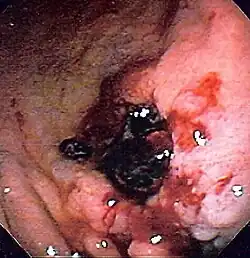

Upper gastrointestinal bleeding is from a source between the pharynx and the ligament of Treitz. An upper source is characterised by hematemesis (vomiting up blood) and melena (tarry stool containing altered blood). About half of cases are due to peptic ulcer disease (gastric or duodenal ulcers).[3] Esophageal inflammation and erosive disease are the next most common causes.[3] In those with liver cirrhosis, 50–60% of bleeding is due to esophageal varices.[3] Approximately half of those with peptic ulcers have an H. pylori infection.[3] Other causes include Mallory-Weiss tears, cancer, and angiodysplasia.[2]

Lower gastrointestinal bleeding is typically from the colon, rectum or anus.[2] Common causes of lower gastrointestinal bleeding include hemorrhoids, cancer, angiodysplasia, ulcerative colitis, Crohn's disease, and aortoenteric fistula.[2] It may be indicated by the passage of fresh red blood rectally, especially in the absence of bloody vomiting. Lower gastrointestinal bleeding could also lead to melena if the bleeding occurs in the small intestine or proximal colon.[1]